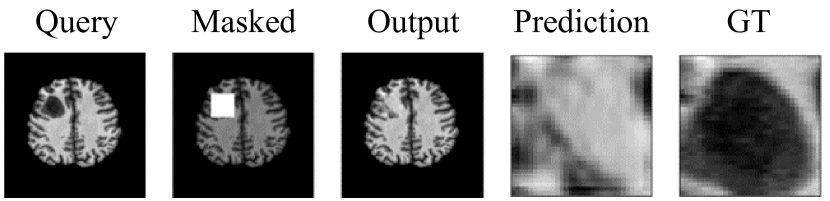

As shown in figure 2, one can see how the problem definition changed according to the amount of data masked. For smaller window sizes, the inpainting network is only required to reconstruct a handful of pixels. However, with larger masks the network is required to reconstruct texture and structure. Additionally, due to adversarial training, the network produces reconstructions without blur.

Figure 5 illustrates snapshots of the sliding window process. The inpainting network restores the masked region to what a normal brain would look like in that area. The inpainting network is naive and does not reconstruct the tumour when partially covered, due to computing L1 loss globally rather than just on the local masked region.